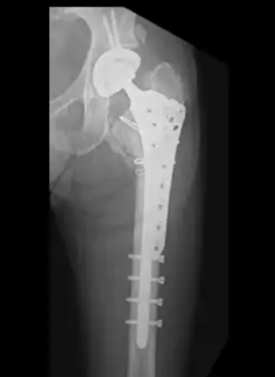

人工股関節置換術の現状とリスク回避

軟骨がほとんど残らない重度の変形では人工股関節全置換術が検討されます。近年の素材改良により耐久性は向上しており、30年以上の維持も期待できるようになりました。

「人工関節は医師が症状の進行度、体重や骨格などから人工関節の機種を含めた計画をたて、それに即した手術を行います。そのため、熟練度の低い医師の場合、サイズが合わず、ゆるみや脱臼などのトラブルが生じることがあります。さらに、人工関節の手術には、感染症や脱臼といったリスクも伴うため、医師選びは大変重要です。人工関節をすすめられた場合、熟練した医師がいる病院でセカンドオピニオンをとることも考え、慎重に意思決定してください」